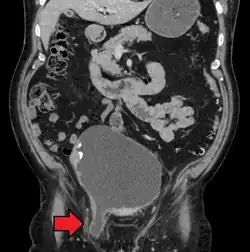

An inguinal hernia which contains part of the bladder. Bladder cancer is also present.

Inguinal hernias mostly contain the omentum or a part of the small intestines, however, some unusual contents may be an appendicitis, diverticulitis, colon cancer, urinary bladder, ovaries, and rarely malignant lesions.[14]